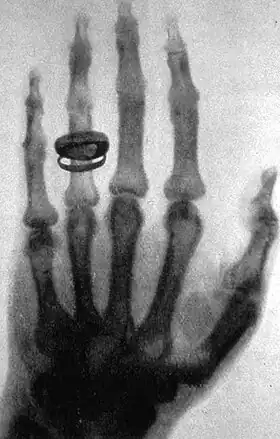

About six weeks after his discovery, he took a picture—a radiograph—using X-rays of his wife Anna Bertha's hand.[6] When she saw her skeleton she exclaimed "I have seen my death!"[14] He later took a better picture of his friend Albert von Kölliker's hand at a public lecture.